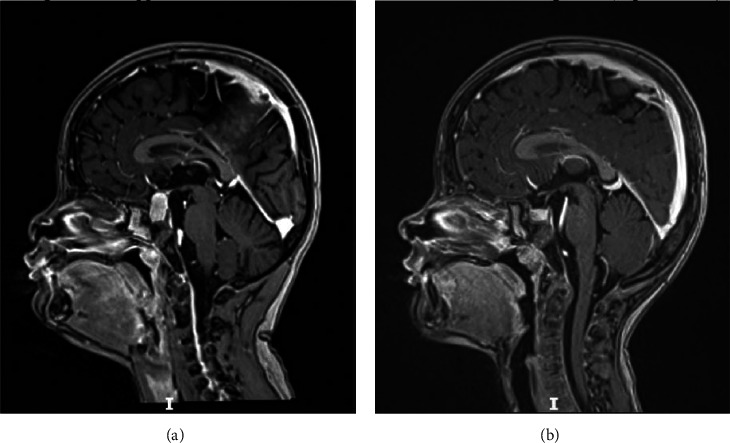

儿童慢性甲状腺功能减退症的主要表现包括生长停滞、骨骼成熟延迟和青春期延迟。1960年,Van Wyk和Grumbach报道了三名患有甲状腺功能减退症的女孩,她们同时患有不完全异性性早熟(乳房发育早、月经初潮、无阴毛)、半乳糖性闭经、骨龄延迟和垂体增大。在接受适当的甲状腺激素替代治疗后,所有异常情况都得到了缓解。多年来,越来越多的病例报道让人们对范-维克-格伦巴赫综合征(VWGS)的临床、生化和放射学表型有了更准确的认识。这些不同的临床表现被认为是独特的病理生理过程所致,而促甲状腺激素(TSH)是其中的关键因素。我们描述了两名患有严重自身免疫性甲状腺炎和 VWGS 的患者(一男一女)的病例。这两名患者的临床、生化和放射影像学特征相似,包括生长发育障碍、无临床甲状腺肿、促甲状腺激素(TSH)浓度明显升高(>100 mIU/L)、检测不到游离甲状腺素水平、甲状腺球蛋白水平 "正常"、促卵泡激素(FSH)和催乳素水平高、青春期前黄体生成素(LH)水平高、骨龄延迟和垂体增生。两名患者表现出差异,尤其是女性患者没有临床青春期发育、中度贫血、肾功能异常以及通过超声波检查发现的中度甲状腺肿。甲状腺素替代疗法逆转了 VWGS 表型和甲状腺功能减退症,患者的生长速度令人满意,甲状腺功能严格正常,6 个月随访时通过磁共振成像检测到垂体大小正常。

The primary manifestations of chronic hypothyroidism in children include growth arrest, delayed skeletal maturity, and delayed puberty. In 1960, Van Wyk and Grumbach reported three girls with hypothyroidism and a combination of incomplete isosexual precocious puberty (early breast development, menstruation, and absence of pubic hair), galactorrhea, delayed bone age, and pituitary enlargement. All abnormalities regressed after appropriate thyroid hormone replacement therapy. Over the years, an increasing number of reported cases has allowed for a more precise understanding of the clinical, biochemical, and radiological phenotypes of the Van Wyk-Grumbach syndrome (VWGS). These varying clinical manifestations are thought to result from a unique pathophysiological process where the thyroid-stimulating hormone (TSH) is a key element. We describe the cases of two patients (a boy and a girl) with severe autoimmune thyroiditis and VWGS. The clinical, biochemical, and radiological imaging characteristics were similar in both patients and included growth failure, absence of clinical goiter, markedly elevated TSH concentrations >100 mIU/L, undetectable free thyroxine levels, "normal" thyroglobulin levels, high follicle-stimulating hormone (FSH) and prolactin levels, prepubertal levels of luteinizing hormone (LH), delayed bone age, and hyperplasia of the pituitary gland. The two patients displayed differences, especially in the absence of clinical pubertal development, moderate anemia, abnormal renal function, and moderate goiter detected via ultrasonography (in the female patient). Thyroxine replacement therapy reversed the VWGS phenotype and hypothyroidism, with satisfactory growth velocity, strictly normal thyroid function, and normal pituitary size detected via magnetic resonance imaging at the 6-month follow-up visit.